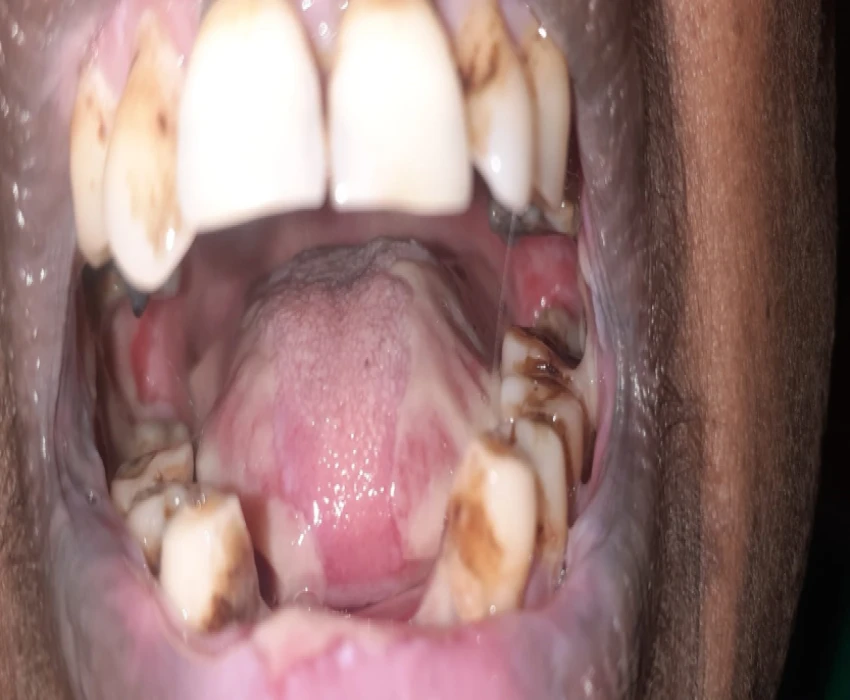

A patient reported to our department with a chief complaint of reduced mouth opening and ulcer in oral cavity since 4-5 months and diagnosed as Pemphigus Vulgaris and was treated for the same.

Pemphigus vulgaris is a blistering disease that initially presents on the oral mucosa in 80% of cases. These intraoral blisters often rupture, leaving painful erosions.